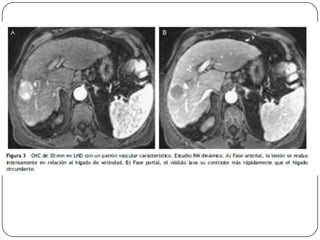

Auxiliares de diagnóstico

 RM

 No utiliza contraste intravenoso

 Es más eficaz que la TC para diferenciar el CH de

nódulos de regeneración

 TAC

 Sensibilidad del 68% con especificidad de 93%, se

utiliza para precisar las alteraciones vistas en el

usg.

Angiografía por resonancia

magnética

 Información sobre la anatomía arterial es útil para

excluir a algunos pacientes de ser tomados en

cuenta para la resección.

 La presencia de un tumor trombi en las venas

hepáticas, vena cava inferior o la vena portal,

pude alterar de forma significativa el enfoque de

tratamiento.

 Las exploraciones dinámicas de TC y de IRM

pueden documentar la relación del tumor con las

venas portales y hepáticas (y, en ocasiones, la

complicación de estas estructuras), delineando

los tumores para los cuales las posibilidades de

Karl RC, Morse SS, Halpert RD, et al.: Preoperative evaluation of patients for liver

curación quirúrgica son remotas.

resection. Appropriate CT imaging. Ann Surg 217 (3): 226-32, 1993